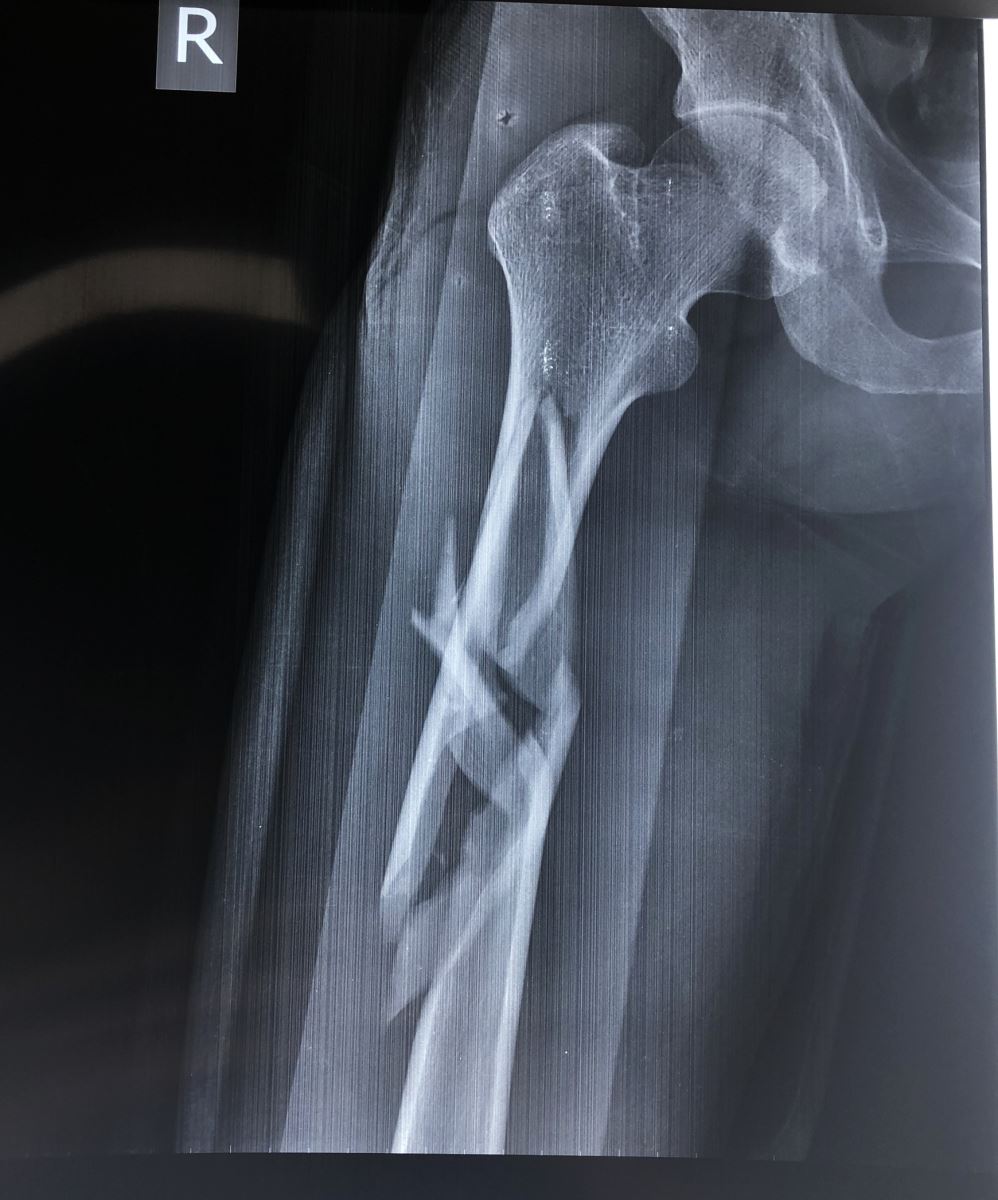

1.2. Đường gãy

Gồm có gãy ngang, gãy chéo, gãy xoắn, gãy 2 ổ hoặc gãy vụn.

- Đường gãy chéo, xoắn: Thường do gập góc kèm theo vặn xoắn cơ thể. Dạng gãy này không vững chắc sau khi nắn

1.3. Sự di lệch

Tuỳ theo vị trí gãy và có các hình thái di lệch khác nhau. Các di lệch thường gặp là gập góc, lệch sang bên, chồng lên nhau, xoay ngoài của đoạn gãy xa.